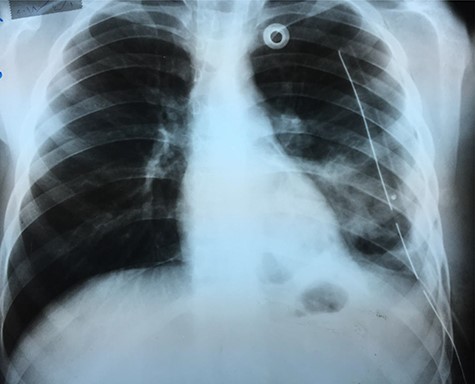

An X-ray image (Fig. 4) was done 24 h after the operation, and it showed good improvement.